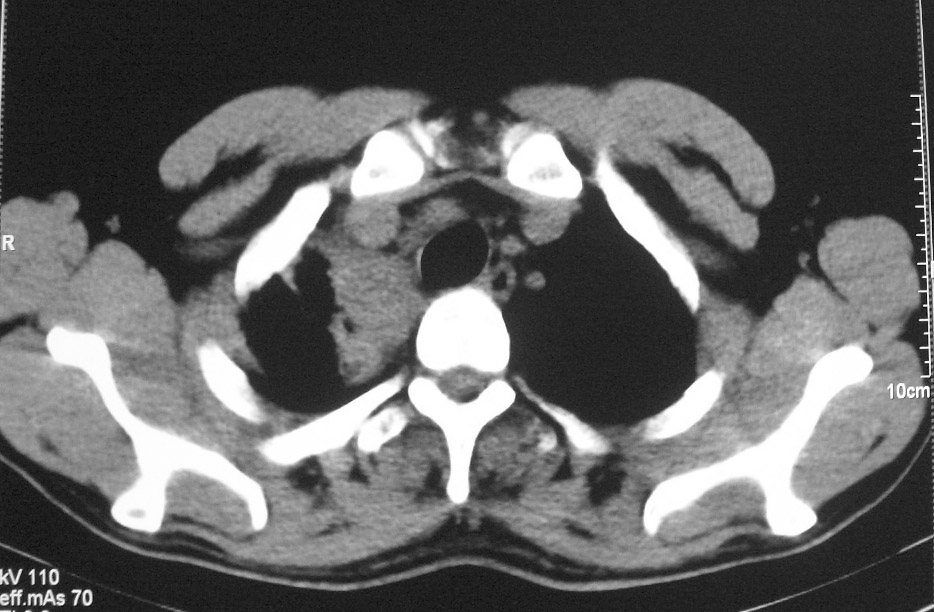

标题: CT5485:[原创]肺部占位请讨论

右上肺ca并肺不张,纵隔淋巴结转移

右肺上叶中央型肺癌并上叶肺不张、纵隔淋巴结肿大

右上叶支气管后壁明显增厚,支持右肺上叶中央型肺癌伴右上叶肺不张、纵隔淋巴结肿大。

考虑右上肺癌并肺不张,纵隔淋巴结转移

右上叶支气管后壁明显增厚,支持右肺上叶中央型肺癌伴右上叶肺不张、纵隔淋巴结肿大。建议支气管镜检查。

右上叶支气管开口变窄,纵隔见肿大的淋巴结。支持右上叶中心型肺癌并右上叶不张纵隔淋巴结肿大。